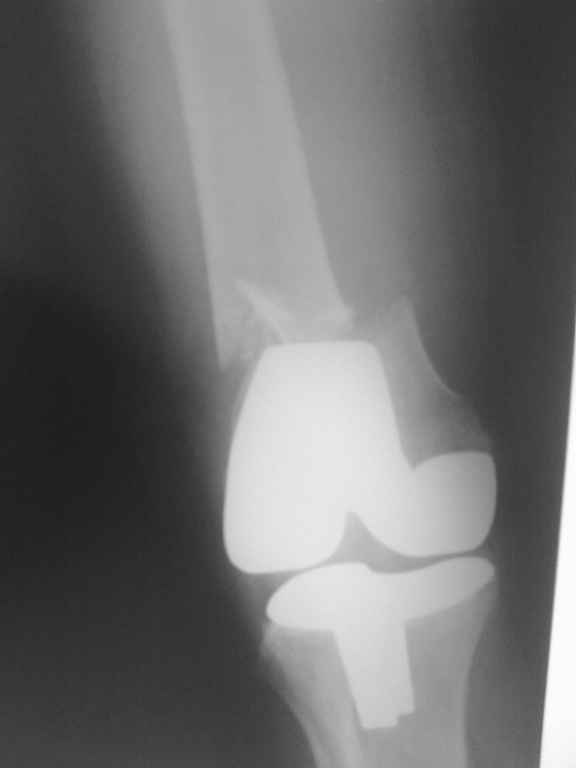

Поступила больная с перипротезным переломом

Перипротезный перелом у пациентки 67 лет . Эндопротезирование год назад . Сопутствующие нарушения ритма сердца и вес 120 кг при росте 185 .Думаю о мыщелковой пластинке с угловой стабильностью рыбинского исполнения остальное больной не потянуть . Заранее всем спасибо !

Уважаемый, Игорь! То что демонсрирует Александр Николаевич, высший пилотаж "neilinga" В нашей стране выполяется единичными спциалистами. Поэтому если не владеете методикой лучше пригласить к себе Челнокова. в случае накостного остеосинтеза, за который говорит ожирение и сопутствующая патология, не используте пластину Рыбинска. она не правильно предмоделирована и невесть из какого металла выполнена.поэтому неизвестно когда сломается при осевой нагрузке, и, кроме того,вы заведомо создадите вальгусную дефомацию, что повлечет за собой расшатывание компонентов. оптимальна в данном случае пластина "Synthes" скоминированными отверстиями. точно титан, идеально предмоделироана, винты надежно блокируются в отверстиях в отличие от Рыбинска.оперировать необходимо на спицевом дистракторе, спицы проводить перпендикулярно оси отломков. после репозиции под онтролем ЭОП чере два доступа пластину максимальной длины.дистальн заблокировать не менее 6 отверстий, проксимально-5.если нет возможности выполнить предложнные варианты, лучше пациентку перевести в отделение высшего уровня.Слишком высоки ставки. С уважением, Сергей.